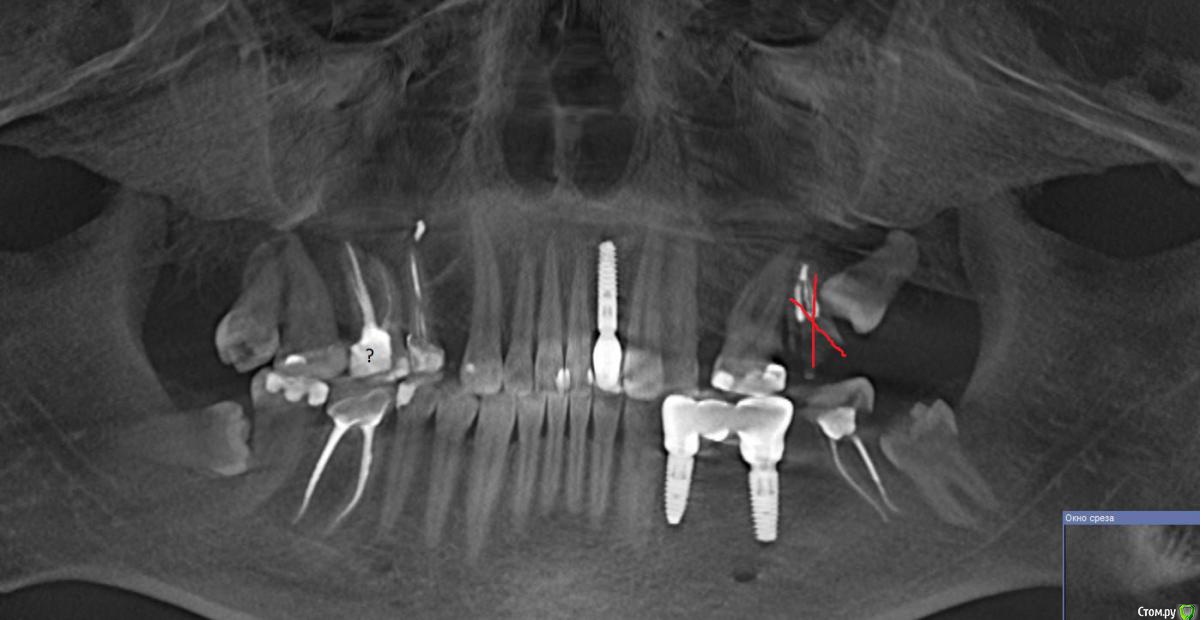

Snarkus Опубликовано 6 марта, 2020 Поделиться Опубликовано 6 марта, 2020 (изменено) Здравствуйте.Прошу консультации по поводу протезирования на 16 зуб.Депульпирован больше 10 лет назад, развился вторичный кариес, рекомендовано ставить коронку. Врач предложил ставить стекловолоконный штифт, и коронку из керамики(?), аргументируя лучшим сохранением тканей зуба. Я сам вижу еще желание продать более дорогой вариант. Подскажите, оправдано ли такое решение, или установка металлокерамики, или даже металла будет разумным достаточным вариантом? (косметические аспекты не интересуют, в приоритете надежность конструкции в долгосрочной перспективе). прикрепил скрин с 3d, для желающих полная версия:https://drive.google.com/file/d/1l4OT-U3-PH0sAFwougB47ObVPbbW_riO/view?usp=sharing Изменено 6 марта, 2020 пользователем Snarkus Ссылка на комментарий